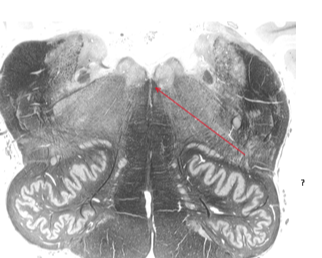

Name this and state its function.

Dorsal efferent(motor) nucleus of Vagus.

Hypoglossal nucleus.

Hypoglossal nerve.

Nerves involved.[3 marks].

Medial longitudinal fasciculus.

oculomotor, trochlear and abducens.